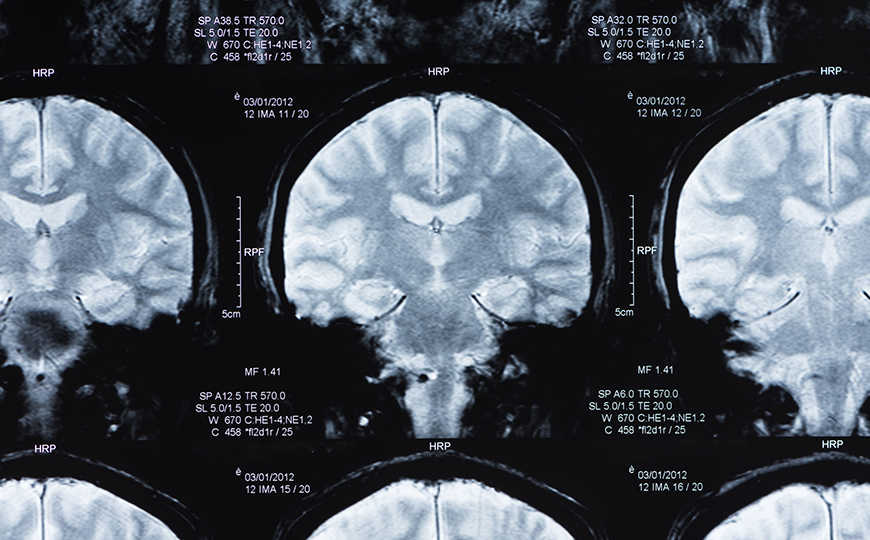

В новой статье в JAMA Neurology ученые выдвинули гипотезу, что прогрессирующая нейродегенерация связана с изменением уровня тау-белка в плазме, и для ее проверки исследовали ассоциаций между этим белком и другими маркерами заболевания, выявленными с помощью ПЭТ и МРТ. В исследовании приняли участие 1 113 человек с разной степенью когнитивных нарушений вследствие болезни Альцгеймера (66%) и без них (34%). Наблюдение за участниками велось в течение нескольких лет. Часть данных взята из баз Инициативы по нейровизуализации болезни Альцгеймера.